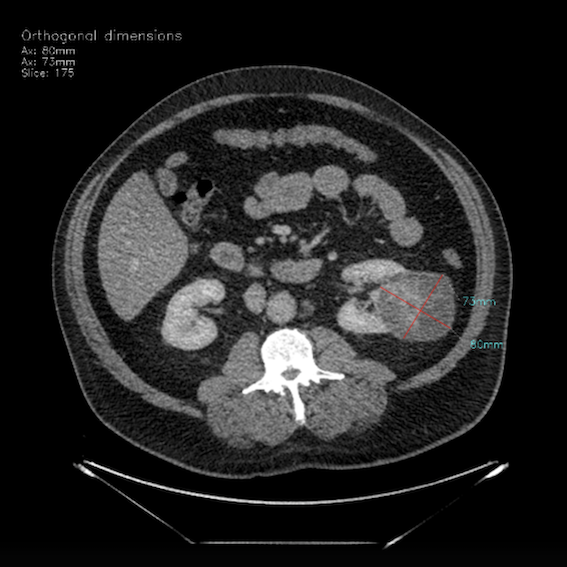

BMVision Kidney

BMVision Kidney represents a novel approach by functioning as both a safety net and a triaging tool in incidental finding pathways for detecting lesions outside the primary field of view for radiologists. This capability ensures incidental kidney cancers and suspicious lesions, often overlooked during routine abdominal imaging, are identified and prioritised for further evaluation.

Kidney Lesion

• Fast and efficient – Radiologists working with BMVision take 33% on average and up to 52% less time to detect, measure, and report kidney lesions from CT scans.

• Accuracy – 96% AI alone

• Sensitivity - 99.2% AI with Radiologist